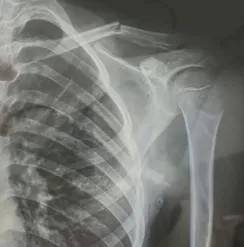

10月30日,内蒙古自治区赤峰市宁城县苏木皋小学一学生家长贾女士给记者打来电话,介绍了孩子被打的原因eth币多少一个。贾女士称,放学通道的墙上有一个电灯的开关,好多孩子放学时都随手去拨弄开关。出于安全考虑,学校和老师都禁止孩子拨弄开关。23日放学时,他儿子和另一个同学调皮,再去拨弄了那个开关,被正在值班的另一个班的班主任发现,把她儿子打了,且打骨折了。

图片由报料者提供